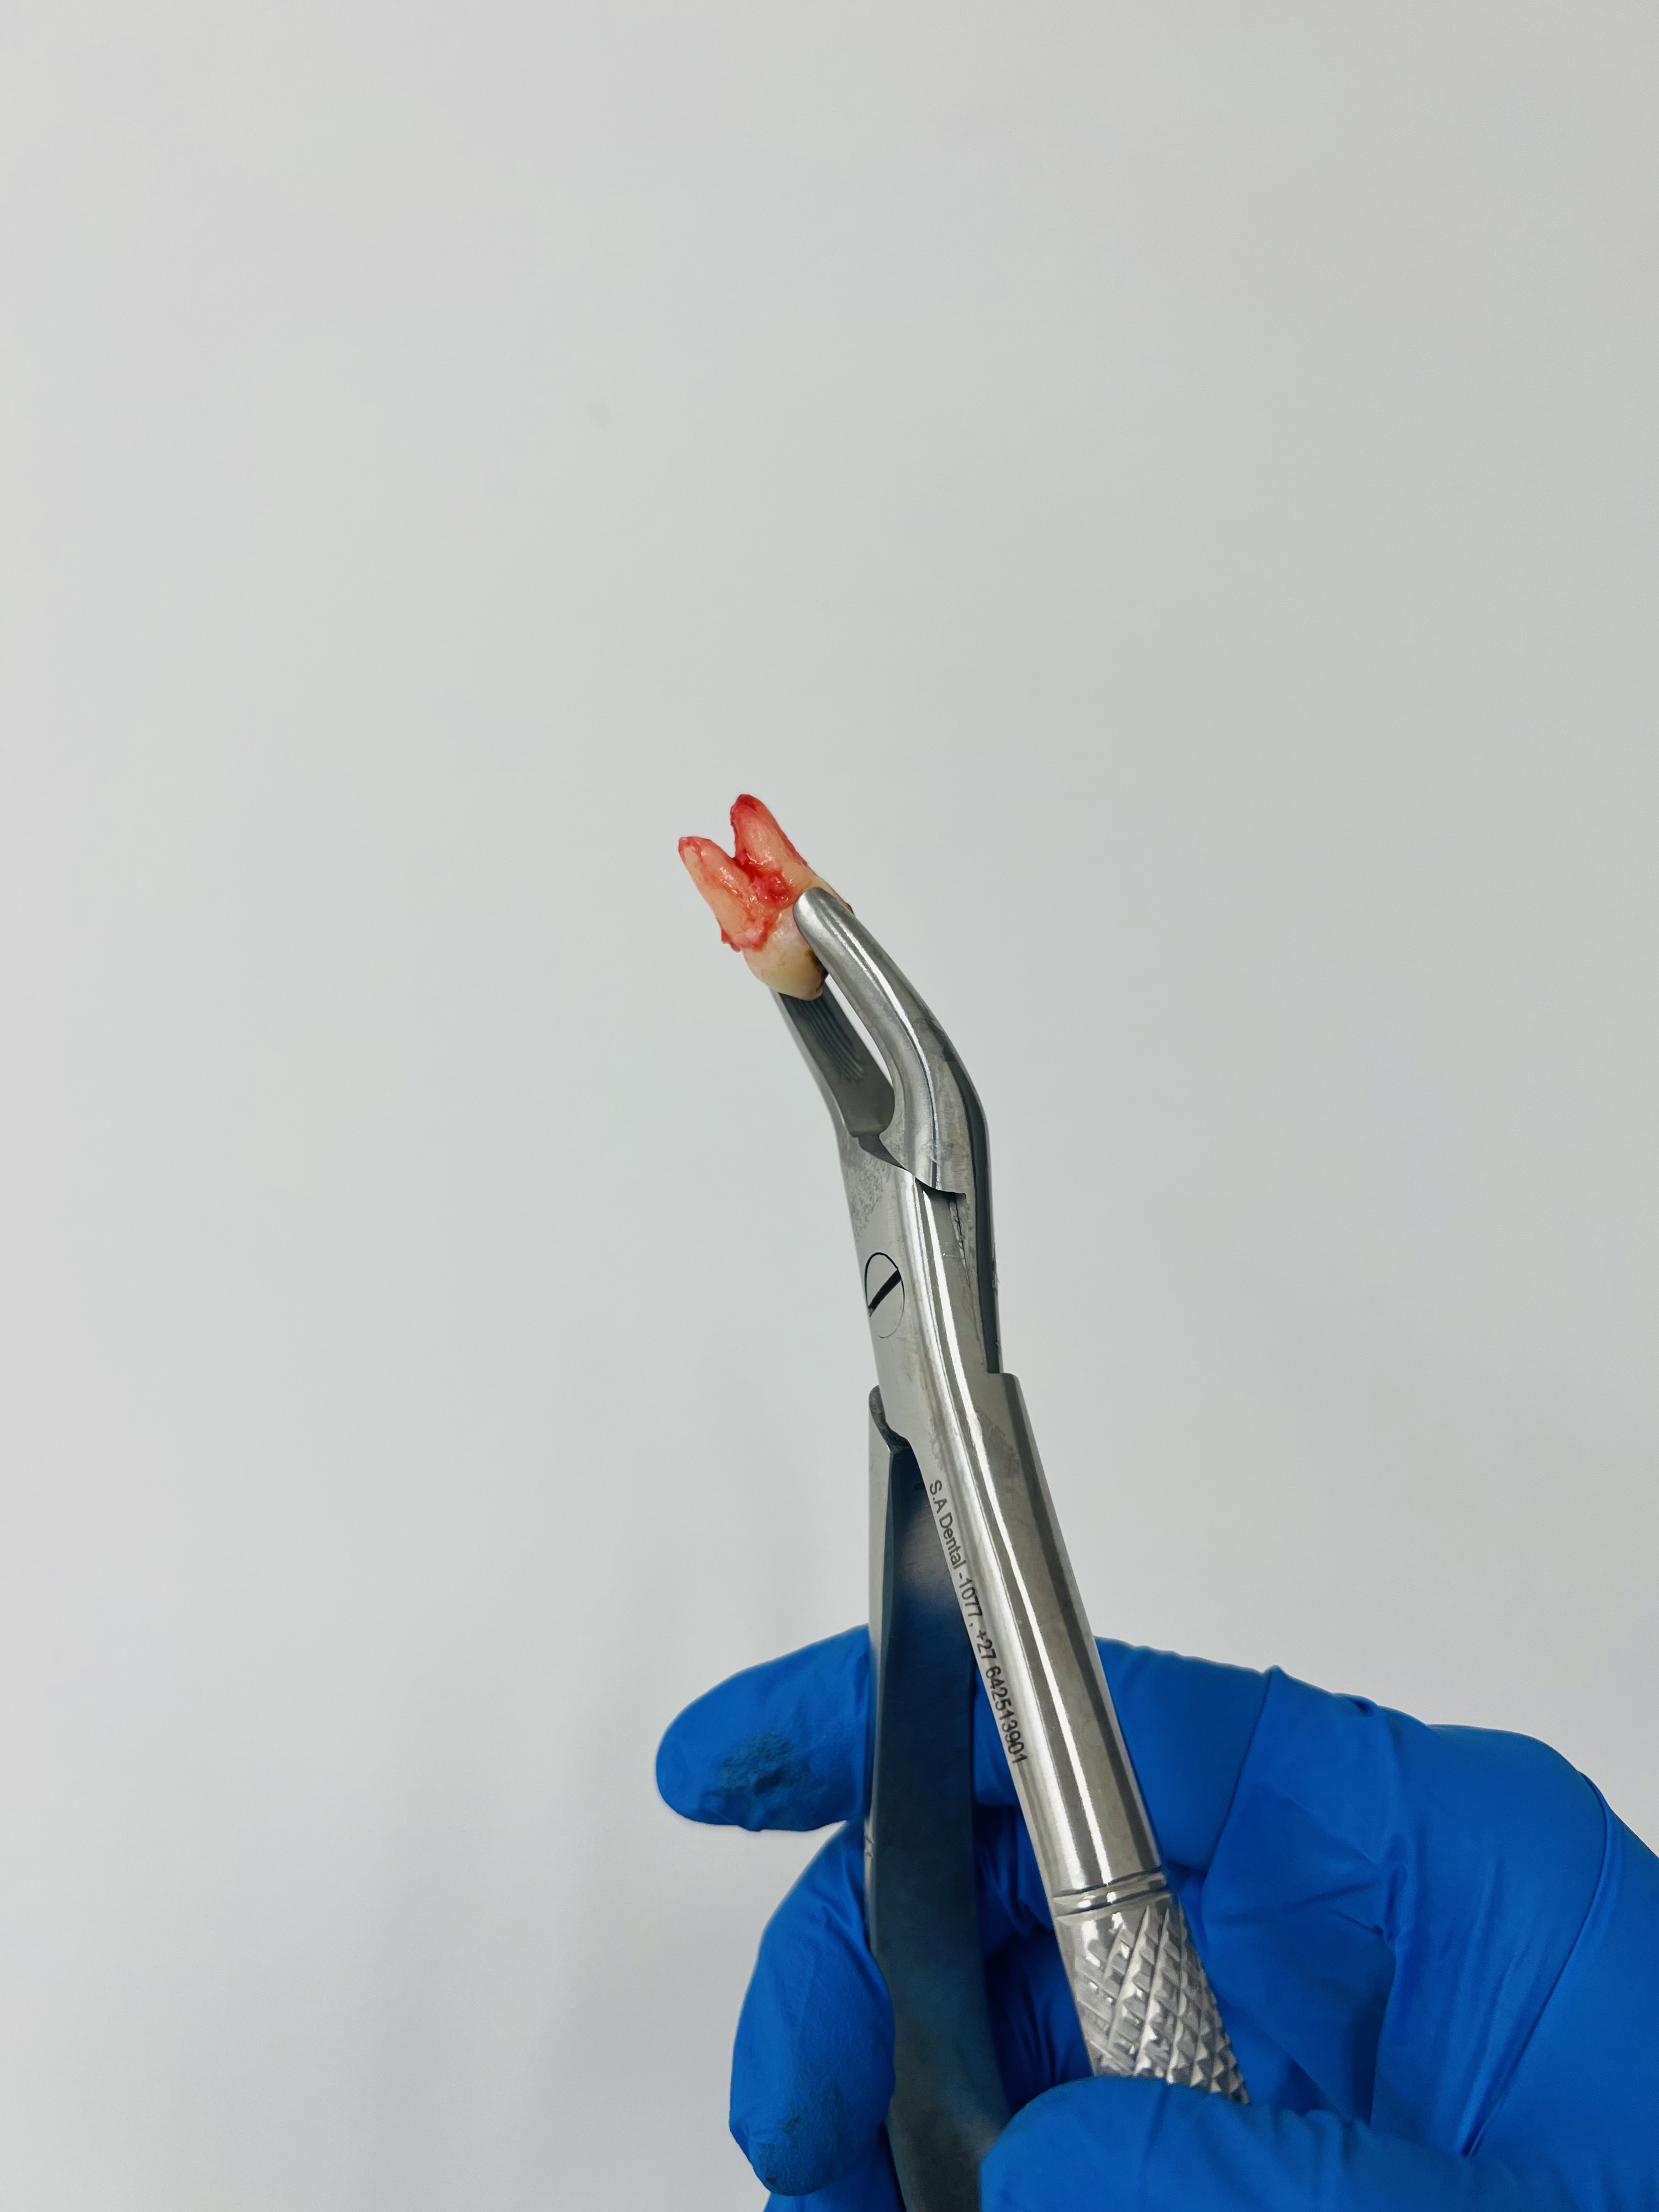

Services

Tooth extraction